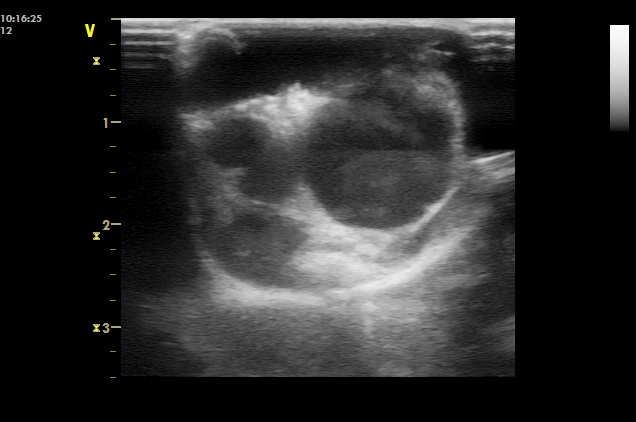

超音波検査で子宮蓄膿症と診断されたゴールデンハムスターにアリジン20mg/kg(SC)を、翌日、8日目、15日目の計4回投与し、抗生物質療法(マルボフロキサシン2mg/kg PO SID 10日間)も併用して治療を行いました。翌日、2回目のアリジン投与時には、わずかな食欲不振と活動の低下を除いて顕著な異常はありませんでした。2回目の投与の翌日にハムスターが通常の食事を再開し、回し車で遊ぶことへの関心がでてきました。外陰部の膿の排出は認められませんでしたが、体重は15gの減少を示しました。2回目の投与後7日目には健康状態が著しく改善し、超音波検査において子宮内腔の液体が消失していました。しかし、子宮壁に嚢胞所見が超音波で観察されたために、投与は継続されました。14日目には、ハムスターは健康で、超音波検査での子宮壁の嚢胞所見も減少していました。補足的な4回目の投与を15日目に行いました。最後の治療から2か月後、ハムスターの健康状態は最適になり、体重は安定し、再び定期的に発情行動が観察されました〔Pisu et al.2012〕。